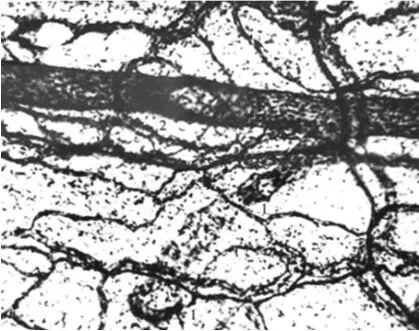

Ангиоархитектоника микроциркуляторного русла брыжейки тонкой кишки: МА, МВ – магистральные артериола и две венулы в одном пучке; ЛС – лимфатический сосуд; ТА – терминальная артериола; СВ – собирательная венула; ЛК и КК – лимфатические и кровеносные капилляры